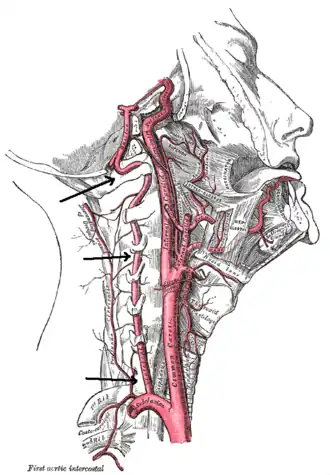

| Arteries of the neck, with arrows indicating the right vertebral artery | |